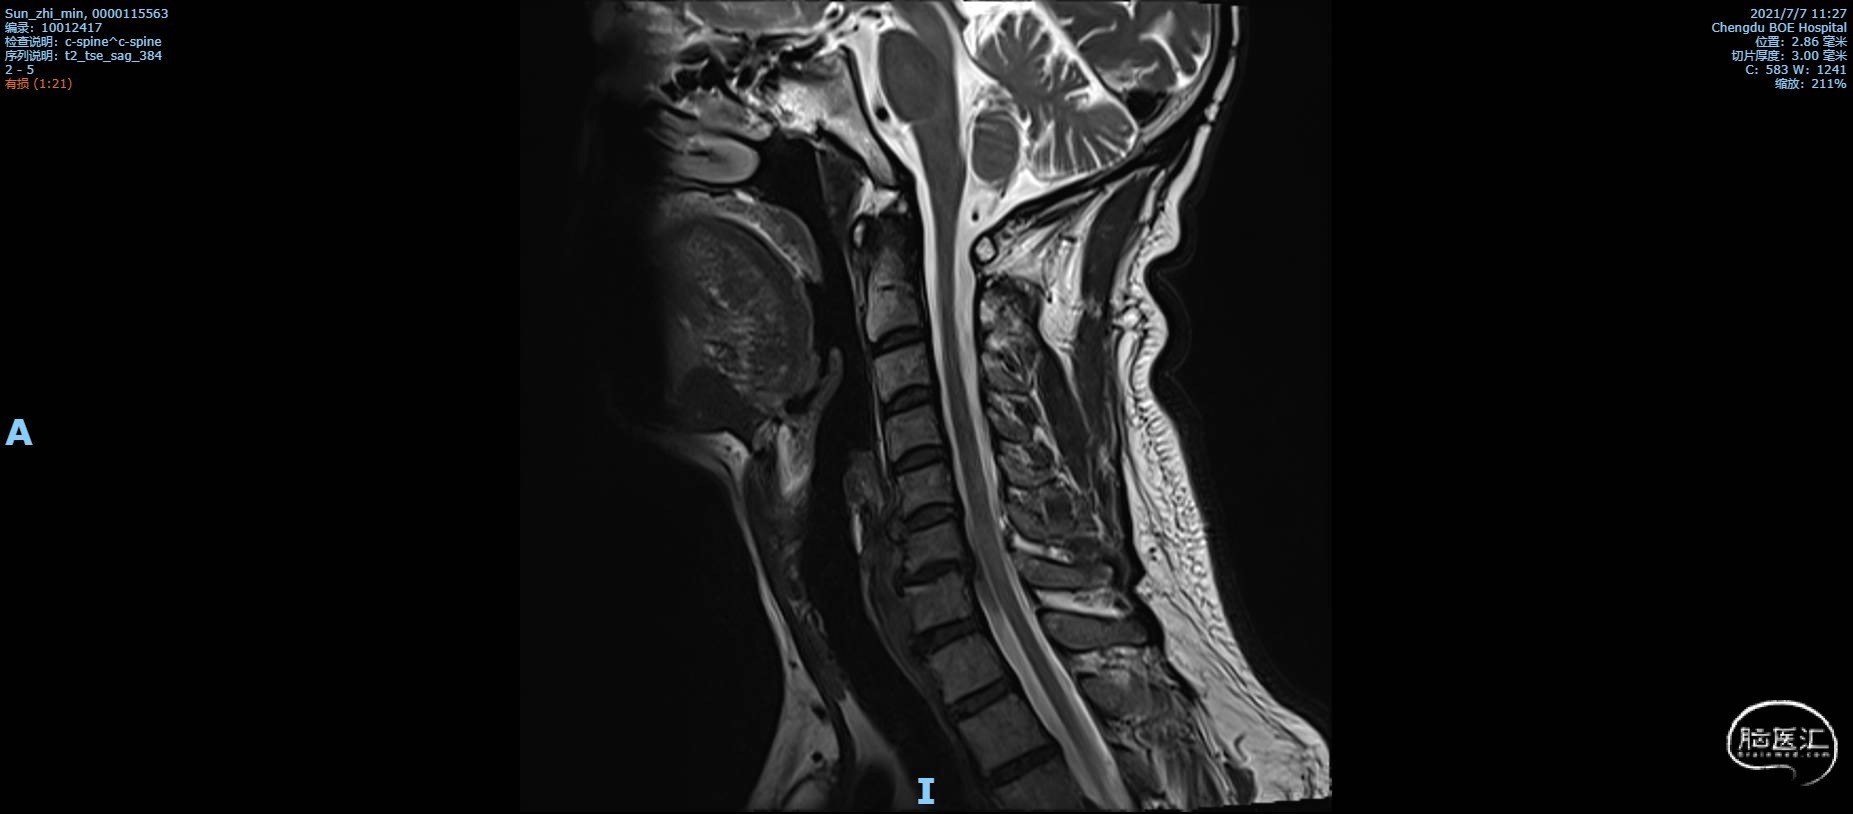

术前复查MRI矢状位颈椎MRI T2 加权像,C6椎体不稳定,C6/C7椎间盘脱出,局部脊髓受压,斑片状信号改变,颈椎管狭窄。

颈椎MRI T2 加权像1

颈椎MRI T2 加权像2

颈椎MRI T2 加权像3